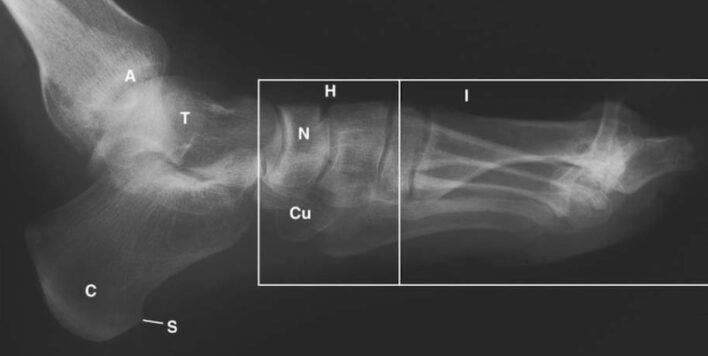

LIÊN HỆ X QUANG

Ghi chú chữ viết tắt:

- A = Ankle; Cổ chân

- C = Calcaneus; Xương gót

- Cu = Cuboid; Xương hộp

- T = Talus; Xương sên

- N = Navicular; Xương ghe

- S =Spur; gai xương (gót)